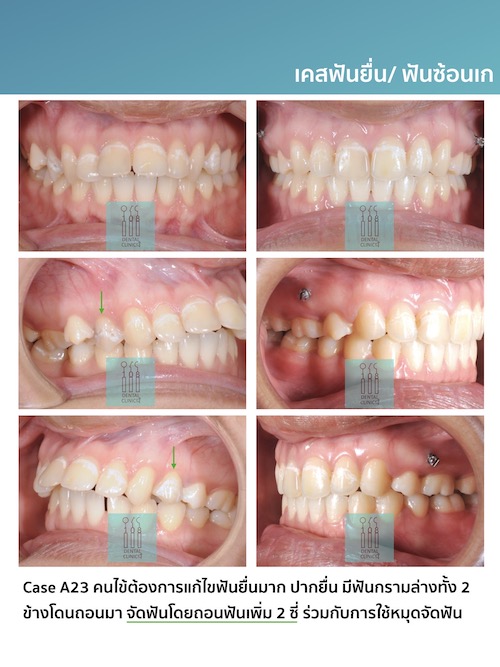

รีวิวเคสจัดฟัน

Review

ติดตามตัวอย่างผลงานเคสจัดฟันของทางคลินิกทันตกรรม 108 ได้ที่

เพื่อให้ทุกๆท่านมั่นใจในคุณภาพการรักษาของทางคลินิก เรายังมีเคสรีวิวอีกมากมายให้คนไข้ได้รับชมและพิจารณานะคะ มาขอดูเคสตัวอย่างแบบชัดๆ 4k retina ไร้ลายน้ำ กันได้ที่เคาน์เตอร์บริการของคลินิกทันตกรรม 108